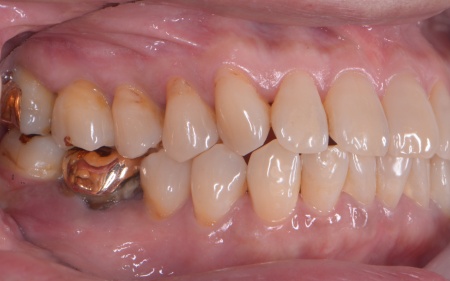

60代女性 重度の歯周病に対して歯周組織再生療法とインプラント治療を施した例

「左右の奥歯がグラグラしていて、固いものが噛みにくい」とご相談いただきました。

拝見したところ、上下左右の奥歯計8本(第1大臼歯、第2大臼歯)に重度の歯周病が認められました。

特に下の奥歯2本(左右第1大臼歯)は歯を支えている骨が著しく減少して歯が大きく揺れており、治療して温存することは難しい状態でした。

また、左上の奥歯(第1大臼歯)は過去に詰め物で治療されていましたが、その下で虫歯が再発しています。